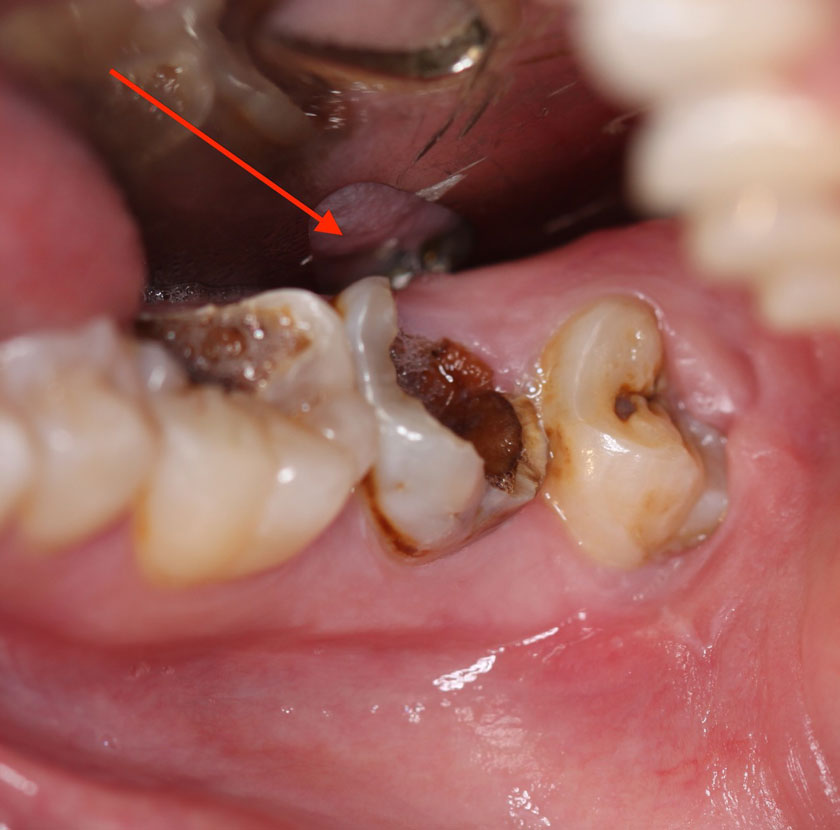

Điều trị tủy răng là một thủ thuật nha khoa nhằm loại bỏ phần mô tủy bị viêm hoặc nhiễm trùng bên trong răng. Tủy răng chứa dây thần kinh và mạch máu – khi bị tổn thương, nó có thể gây đau nhức nghiêm trọng và dẫn đến nhiều biến chứng nếu không xử lý kịp thời.

Viêm tủy răng

Bạn có thể cần điều trị tủy nếu gặp các dấu hiệu sau:

Nếu không điều trị kịp thời, tình trạng viêm tủy sẽ chuyển thành nhiễm trùng nặng hơn.